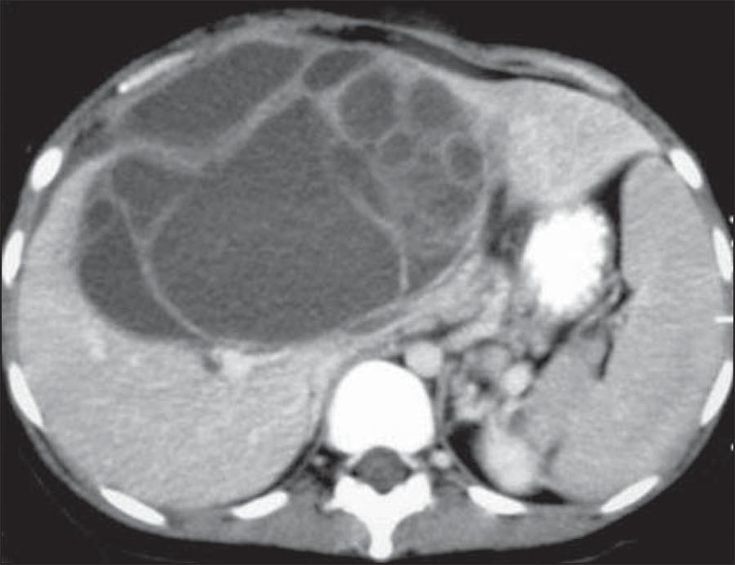

hemangioma

hemangioma: mais comum, hiperproliferação vascular

us com lesão homogêna e hipoecóica

tc: enchimento precoce da perifeira padrão centripeto wash-in (globuliforme). Na fase tardia, lesão hiperintensa (no adenoma é hipodensa)

T1: hipointenso

T2: hiperintenso em relação ao parênquima hepático, mas menos intenso que o liquor

T1 com gadolíneo: realce periférico nodular descontínuo que progride de forma centrípeta nas imagens tardias

T1 com contraste hepatoespecífico: apresentam uma ampla gama de aparências, tornando esse método menos útil.

Na fase hepatoespecífica, pode apresentar pseudo-washout (aumento da captaçaõ de contraste pelo parênquima hepático adjacente)